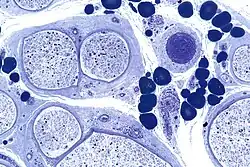

| Micrograph showing a vasculitic peripheral neuropathy; plastic embedded; Toluidine blue stain | |